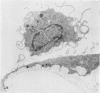

A method is described for the culture of isolated intact mouse glomeruli. Cultures showed adherent glomeruli after 2 days and from 2-4 days a monolayer of cells began to develop around the points of adherence. The predominant cell (Type I) was 80-200 micrometer in diameter with cytoplasmic extensions, later becoming polyhedral and often multinucleated. Type II spindle cells, 70-100 micrometer in length, were less prominent in the earlier stages and later formed sheaves between Type I cells. Small phagocytic Type III cells, 10-20 micrometer in diameter, were not prominent in cultures from normal kidneys and tended to form small clusters on top of the Type I cell monolayer.